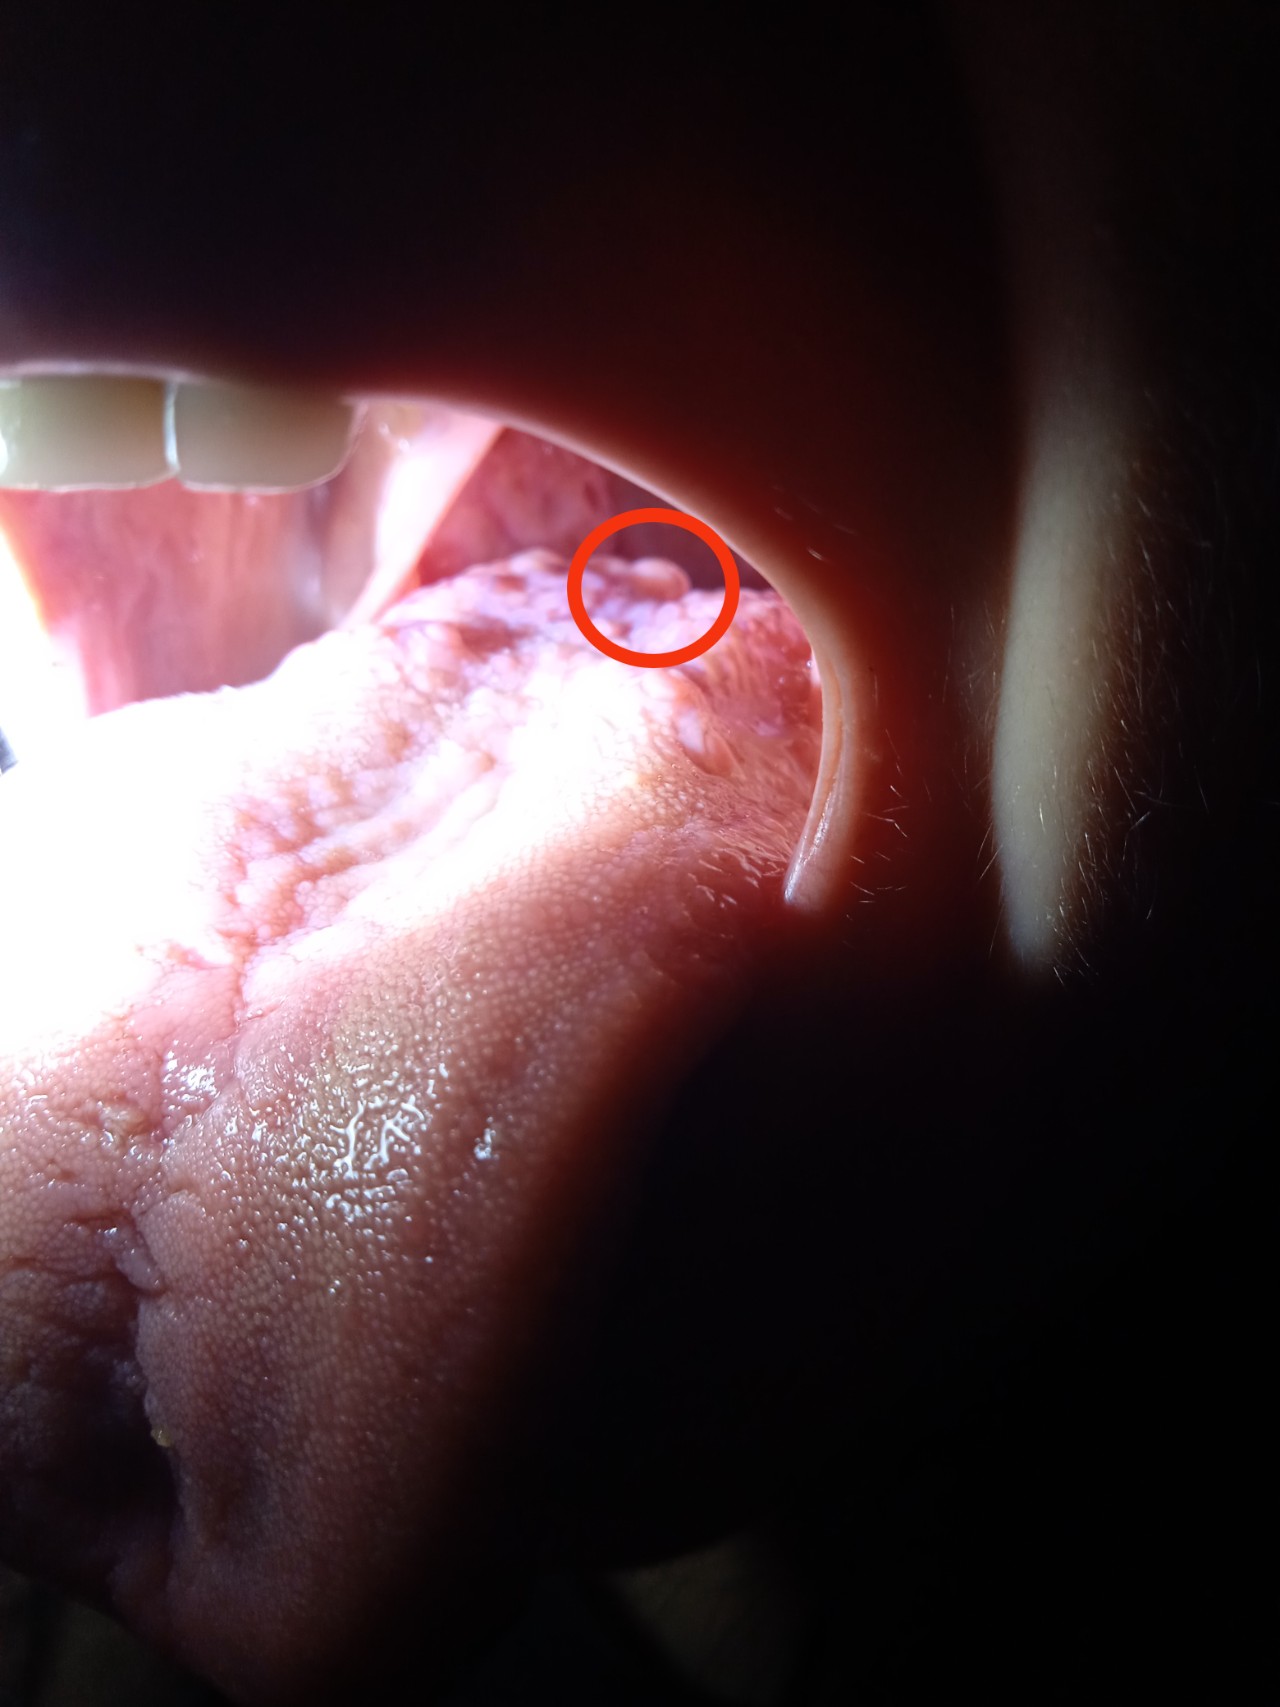

В вівторок випадково знайшла утворення на корені язика. Роздивитися і взагалі помітити його важко. На фото обвела червоним кільцем. В середу вже було важче говорити.

Була в сімейного лікаря, та направила до ЛОРа, сама не змогла роздивитися утворення. В ЛОРа була вчора, лікар направила до ЛОРа-онколога, теоретичний діагноз - папілома, 0.5 мм. Огляд лором-онкологом аж у понеділок, але зараз мене дуже болить шия там, де всередині з правої сторони знаходиться це утворення, часом охрипаю, напружувати горло і довго говорити не можу.